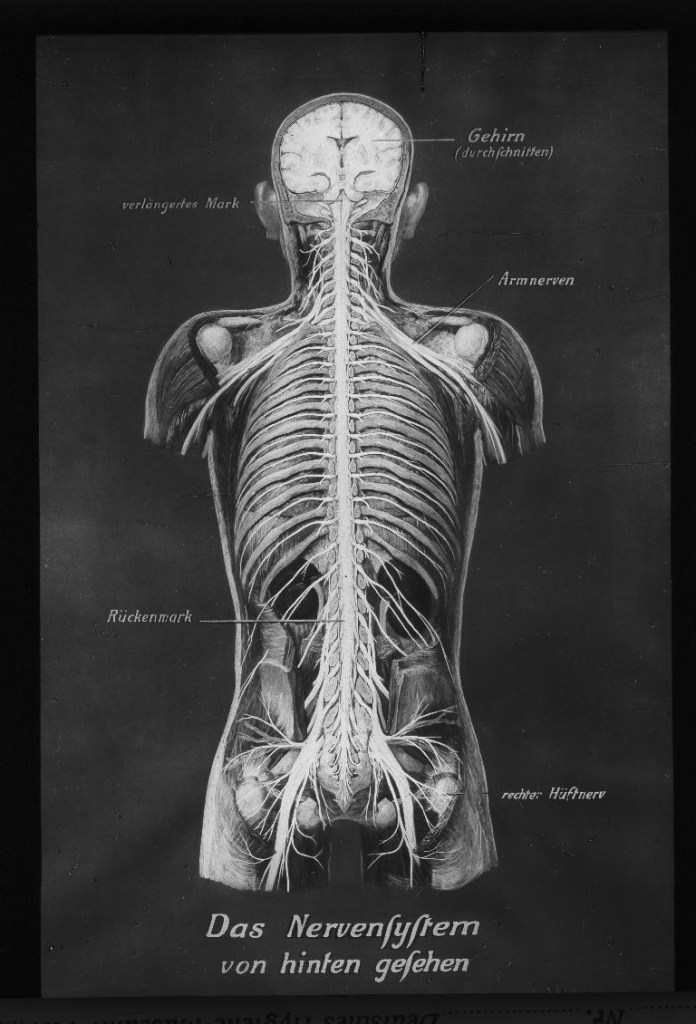

Auch mikroskopische Darstellungen wurden gezielt eingesetzt, um naturwissenschaftliche Erkenntnisse und medizinische Theorien über die Gefahren des Alkoholkonsums für die Allgemeinheit sichtbar zu machen.

Wissenschaftliches Anschauungsmaterial legte dar, dass selbst der Konsum geringer Alkoholmengen für Körper und Geist schädlich sei und folglich eine Bedrohung für das „Volk“ sowie die Volkswirtschaft darstellen würde. Diese Darlegung wurde durch eine wissenschaftliche Beweisführung visualisiert und legimitiert.

Demgemäß geht auch aus dem Bildmaterial hervor, dass der Kampf gegen den exzessiven Alkoholkonsum weniger individuellen gesundheitlichen Aspekten galt, sondern vor allem auf eine funktionierende, nüchterne Arbeiterschaft abzielte, die verlässlich eine gute Arbeitsleistung erbringen könnte. Wissenschaftlich fundierte Untersuchungen, statistische Ergebnisse und graphische Darstellungen untermauerten die zentralen Aussagen der alkoholgegnerischen Aufklärungsarbeit.